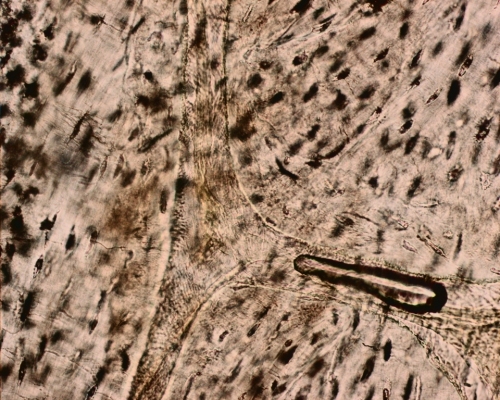

Ground section of bone

Ground section of bone  Sketch of bone